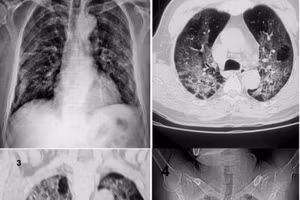

Hình ảnh tổn thương phổi hậu Covid-19. Ảnh: BSCC.

Nguy cơ xơ phổi hậu Covid-19

GD&TĐ - Xơ phổi là hậu quả của phản ứng viêm. Trong đó, có hai con đường chính dẫn đến tình trạng này. Nguyên nhân đầu tiên là nhiễm virus gây tổn thương trực tiếp đến phổi.